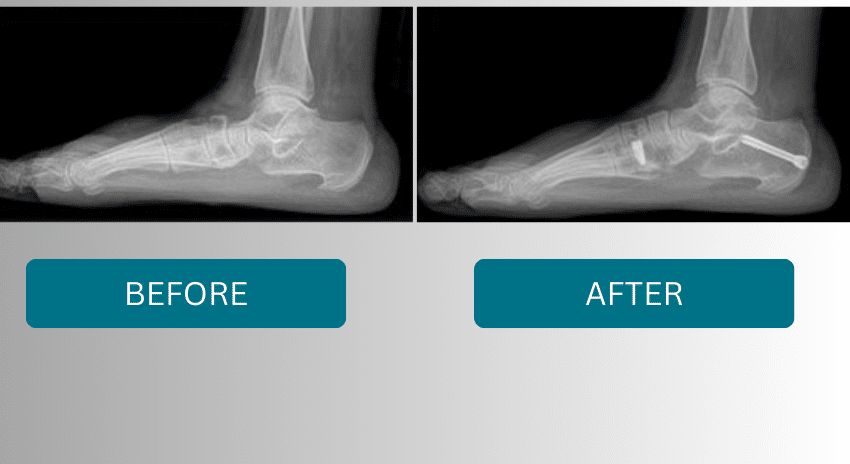

Flat foot reconstruction with tendon transfers and osteotomies.